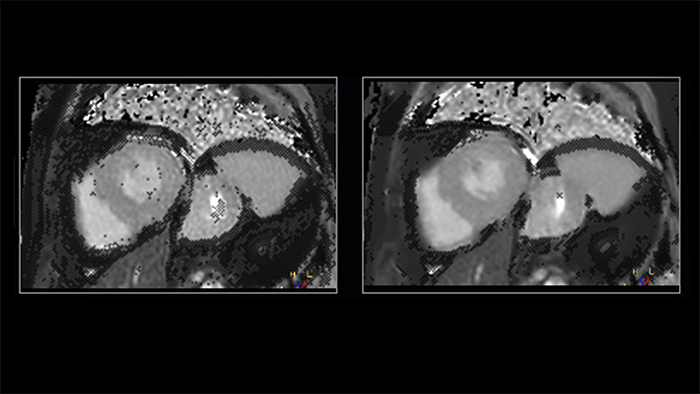

Shorter data readouts [2] enabled by Compressed SENSE provide benefit for black bloods and T1 mapping as well with sharper images acquired. For T1 mapping this results in fewer unconfident pixels on the resulting T1 map (see Fig. 3).

Figure 3. T1 mapping: shorter readouts using C-SENSE x3 leads to fewer unconfident pixels. Left to right: SENSE x2, C-SENSE x3